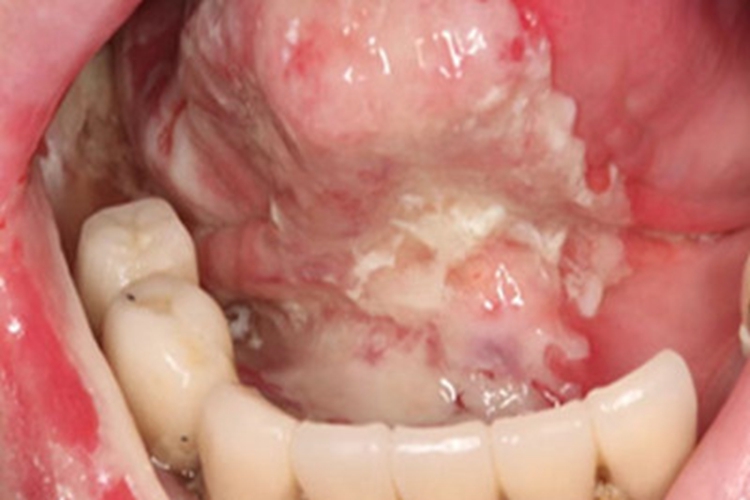

牙龈癌可能与口腔卫生不良、不良修复体有关,可见患者牙龈出现白斑,形状不规则,底部有红色糜烂面,患者需及时就医治疗。

牙龈癌可累及牙龈出现白斑表现,白斑表面凹凸不平,形状多不规则,白斑是溃疡面上附着的一层白膜,去除白膜可出现鲜红色的糜烂面。